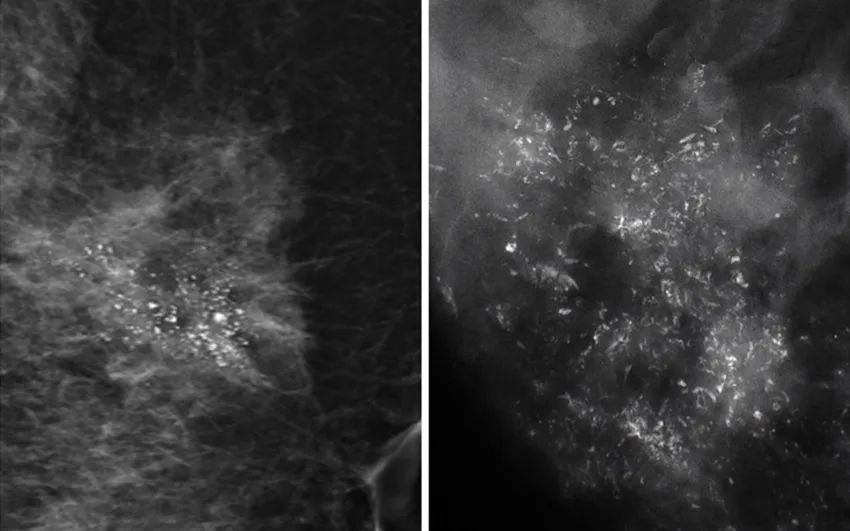

當癌細胞不受控制地生長,這一群癌組織會變得很擁擠,導致里面小部分的細胞會因組織缺氧而壞死。這時,我們身體無法清除壞死的組織,這些細胞就變硬而形成鈣化點。

因此,惡性鈣化點的特點是:聚集很緊密,簇聚于局部區(qū)塊,且鈣化點很小,形狀不規(guī)則,每個點都不太一樣,或有針尖狀、小桿狀、分叉狀、簇狀及泥沙樣多屬于惡性病變。